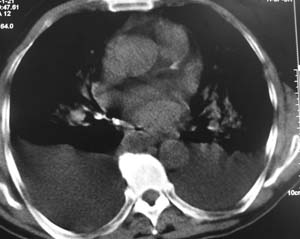

以下是引用陈维松c在2007-1-21 13:45:00的发言:[br]心衰肺水肿,胸腔积液。

以下是引用zyx168在2007-1-21 17:08:00的发言:[br]男,71岁,咳嗽、胸闷10天余,咯血1天。[br]两肺大片状密度均匀影,充气支气管征象明显,左房增大,双侧胸腔内新月形液性密度影。[br]考虑:1,心源性肺水肿伴双侧胸腔中等量积液;[br] 2,两肺肺炎?